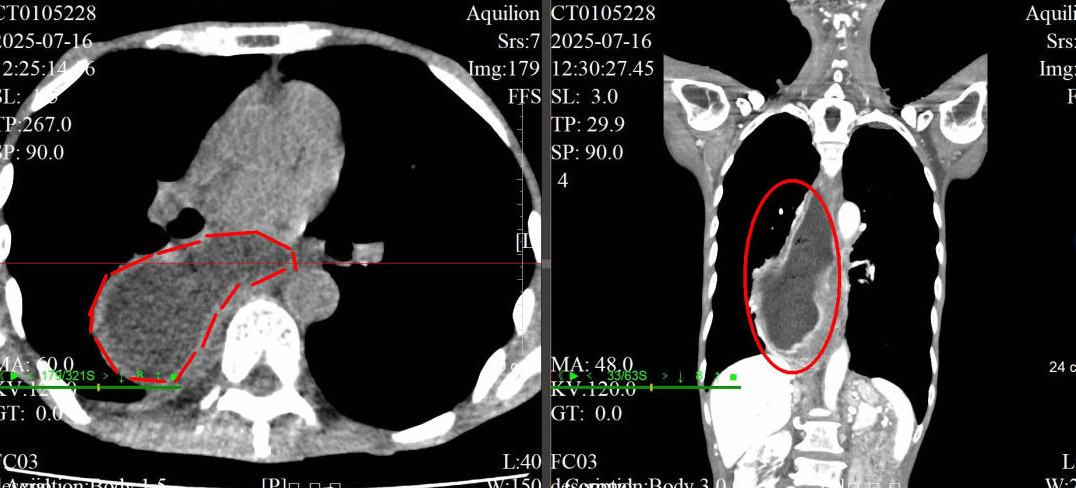

CT水平面和冠状面显示,老伯的食管严重扩张,形成了巨大的憩室,已经不是正常的“管状”了。

据悉,周老伯所患的是极为严重的“贲门失迟缓症”,并伴有巨大的食管憩室和溃疡。他的食管已然变形,全程严重扩张,丧失了基本功能,就像一条“死胡同”。食物无法顺利进入胃部,积聚在巨大的食管内,导致他反复呕吐、营养不良,最后甚至连水都难以下咽。